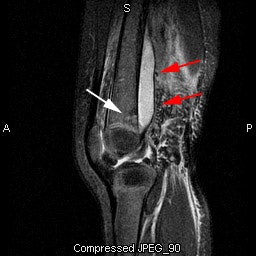

Pediatric osteomyelitis: The case below is from a 19 month old infant who presented with left leg pain. The leg was externally rotated and initially the child was thought to have a septic hip- however, a hip ultrasound was negative. A bone scan was ordered to evaluate for osteomyelitis. The flow images showed mild hyperemia in the left distal femur (click here to view flow images), but there was an elliptical area of abnormal activity on blood pool images involving the distal left femur (blue arrows). The delayed images did not reveal a significant focal finding and were interpreted as negative. The blood pool abnormality was felt to be related to a soft tissue infection. Because of a high degree of concern, an MR exam was then performed. The MR demonstrated a large subperiosteal pus collection (red arrows) and a small focus of osteomyelitis in the distal left femoral metaphysis (white arrow). This is an example of a false-negative bone scan in pediatric osteomyelitis. The late phase bone scan images may have been negative due to the small size of the focus of infection or due to imaging during the transition from "cold" to "hot" osteomyelitis. |